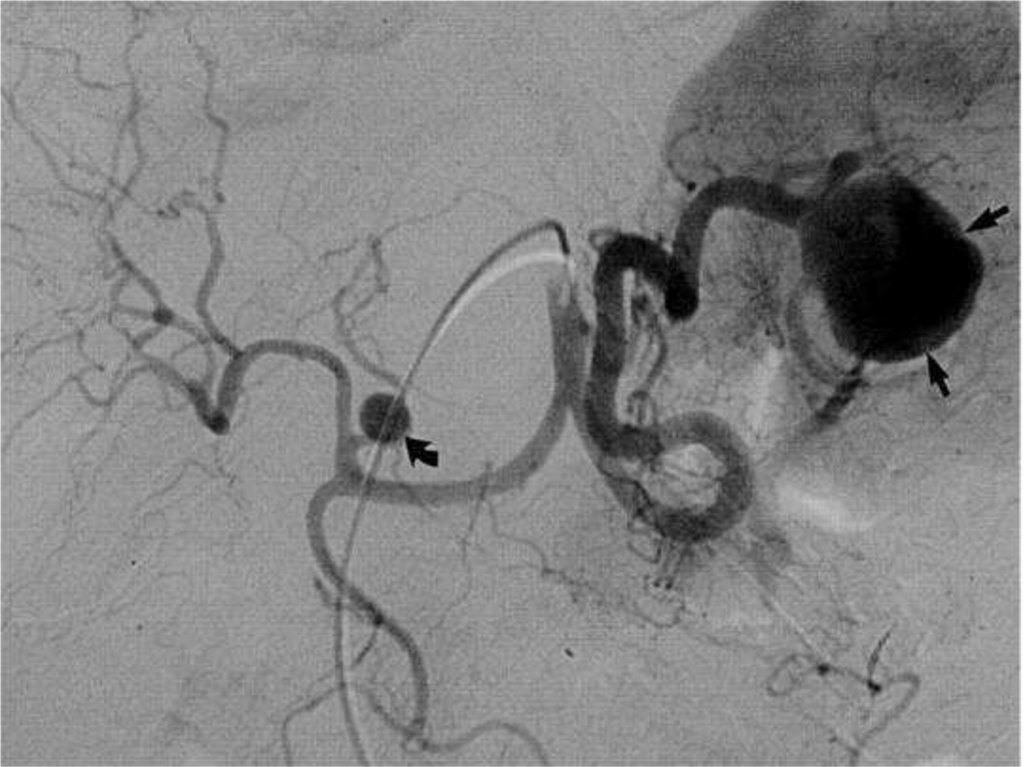

14. 1. Короткие желудочные артерии 2. Левая желудочно-сальниковая

15. По калибру селезеночная вена превышает артерию в 1.5-2 раза